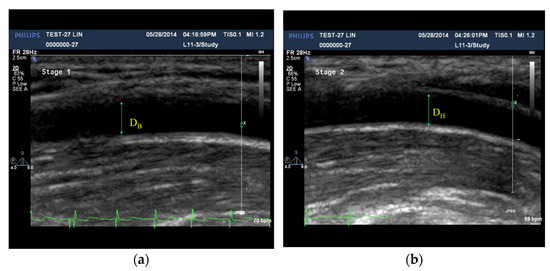

2.1. Assessment of FMD Using the Ultrasonography

| DB,max (cm) | DH,max (cm) | p-Value | DB,min (cm) | DH,min (cm) | p-Value | |

|---|---|---|---|---|---|---|

| Control | 0.323 ± 0.057 | 0.348 ± 0.060 | 0.001 | 0.297 ± 0.055 | 0.321 ± 0.056 | 0.116 |

| Patient | 0.400 ± 0.057 | 0.422 ± 0.220 | 0.002 | 0.350 ± 0.052 | 0.380 ± 0.052 | 0.302 |

| p-value | 0.001 | 0.004 | 0.018 | 0.015 |